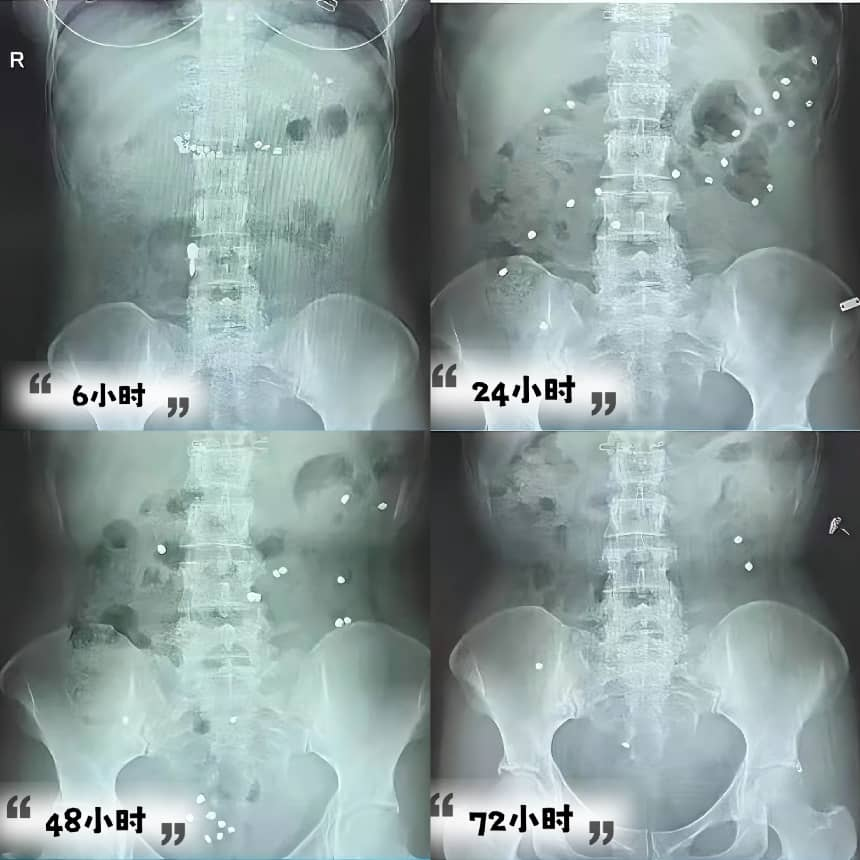

4.服药拍片:

• 第1天:清晨空腹或早餐后1小时,温水吞服2粒胶囊(不可咀嚼哦!)

• 拍片时间:服药后6小时、24小时、48小时、72小时分别至一楼放射科拍摄腹部X线片,最后一次拍片结束1小时在自助机领取报告

四、结果分析:肠道“慢不慢”一看便知!

1.正常:48小时残留率≤20%,肠道传输效率满分!

2.慢传输型便秘:48小时残留率>20%,标记物均匀分布于结肠

3.出口梗阻型便秘:48小时残留率>20%,标记物集中于直肠

4.混合型便秘:残留标记物分散在结肠且有集中于直肠或乙状结肠,需进一步检查